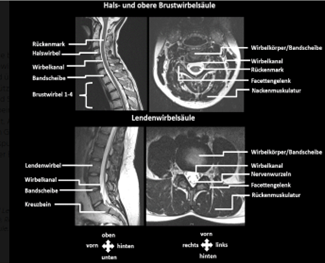

Die Wirbelsäule – der Aufbau und die Darstellung im MRT

Die menschliche Wirbelsäule besteht aus verschiedenen Regionen, der Halswirbelsäule, der Brust- und der Lendenwirbelsäule. Im Hinterkopfbereich bildet die Halswirbelsäule mit dem Schädel/ Kopf gelenkartige Verbindungen und im unteren Rückenbereich verbindet sich die Lendenwirbelsäule sehr fest mit dem Kreuzbein und dem Becken. Zwischen den Pofalten bildet das Steißbein die Forsetzung des schon nicht mehr beweglichen Kreuzbeins und hiermit das Ende der Wirbelsäule.

Die Wirbelsäule selbst besteht aus vielen Bestandteilen. Die knöchernen Strukturen nennt man Wirbelkörper, eine typische Wirbelsäule hat sieben Halswirbel, zwölf Brustwirbel und fünf Lendenwirbel. Die einzelnen Wirbelkörper sind über Bänder und die sogenannten Bandscheiben gelenkig miteinander verbunden. Im hinteren Bereich gewährleisten jeweils zwei Facettengelenke Rotations-, Scher- und Knickbewegungen. Die Wirbelkörper und Wirbelbögen bilden einen Kanal. (Abb 1) Dieser „Spinalkanal“ beinhaltet das Rückenmark, das sich von Halswirbelsäule bis in die untere Brustwirbelsäule erstreckt und dort die pferdeschweifartigen Nervenwurzeln in den Lendenwirbelkanal abgibt erstreckt. Zwischen zwei Wirbeln treten im Nervenwurzelaustrittloch jeweils rechts und links zwei Nervenwurzeln aus, die Signale über Körperfunktionen vom Gehirn zu einzelnen Körperteilen und von dort  wieder zurück transportieren. Die Austrittsstellen der Nervenwurzeln stehen in enger nachbarschaftlicher Beziehung zum Faserring der Bandscheiben und zu den Facettengelenken. Somit kann man anhand der engen Lagebeziehung gut verstehen, wenn Abnutzungsprozesse im Bereich der Bandscheiben oder der Gelenke bestehen, Nervenwurzeln gedrückt werden können und hier dann auch entsprechend Schmerzen, störende Gefühlsstörungen, Kribbeln, Taubheit oder Lähmungsgefühle entstehen können.